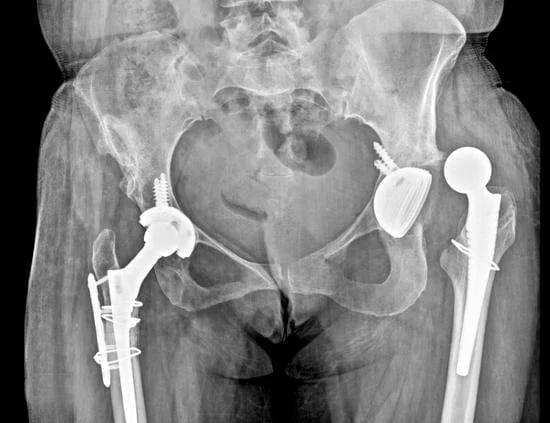

Quality and affordable healthcare has long been the essence in the field of medical sciences & treatment. Every patient expects an early diagnosis and a planned approach to treatment procedures with affordability and access to quality healthcare. Knee replacement, Hip replacement, Fracture treatment are being done by Dr.P.Sankaralingam at very affordable costs without compromising on quality.

• Hip & Knee Replacement and Revision Surgeries